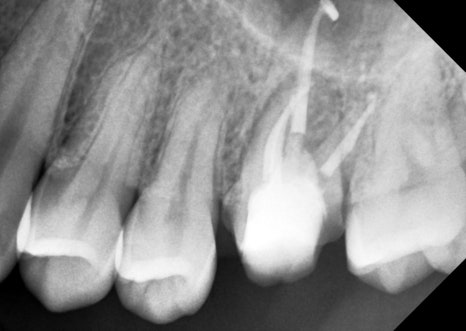

크라운 시적 엑스레이

통증도 완전히 사라지셨고

염증도 서서히 잡혀가고 있어서

만들어온 크라운을 시적해보고

엑스레이를 다시 찍었습니다.

치아 뿌리와 크라운 경계가

턱이 지지 않고

스무스하게 잘 연결됐는지

평가하는 거예요.

턱지지 않고 잘 만들어져서

바로 붙여드렸습니다.